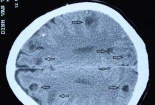

Phát hiện gần 50 ổ sán trong não bệnh nhân